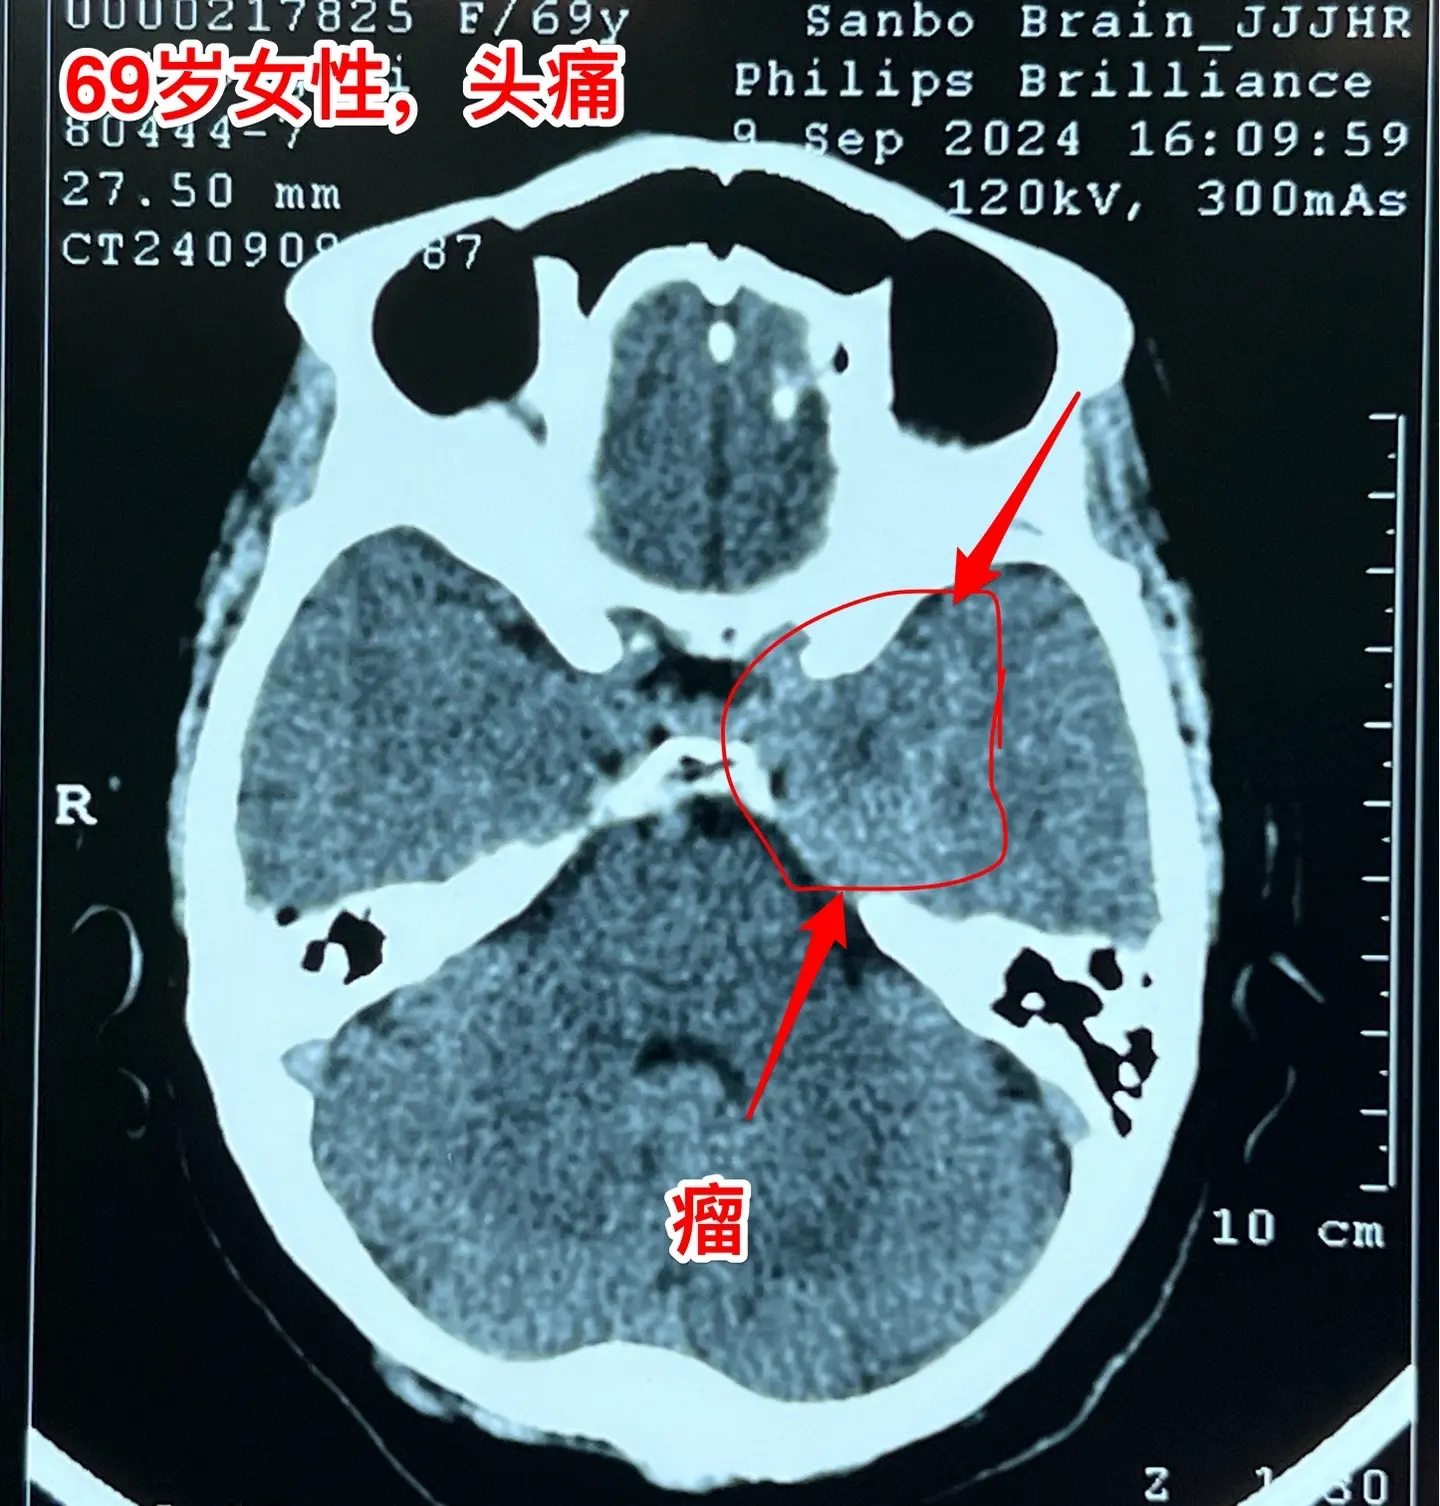

海绵窦区神经鞘瘤,是良性肿瘤。69岁青岛市老太太经常感到头痛,不太剧烈,没有专门去检查。九月份检查脑部磁共振发现左侧海绵窦长了肿瘤。在我院住院后作了强化磁共振,看见左侧海绵窦内有个大肿瘤,见图,考虑是神经鞘瘤,神经鞘瘤是良性肿瘤,如果完全切除了就可以治愈。 老太太有两个女儿,积极要求给她作手术。69岁年龄还是有点大,手术是有风险的! 9月12日下午四点开始进入手术室,手术持续到13日凌晨才结束。手术过程很顺利,肿瘤得到完全切除。今天看见老太太精神比较好,准备下地行走。神经鞘瘤海绵窦